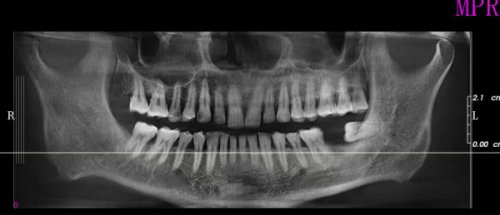

北京中诺口腔医院作为正规的三等级医院,在口腔医疗领域有着良好的口碑。它的种植牙项目更是备受患者青睐。医院的种植团队会在术前对患者进行全方面的口腔检查和评估,包括口腔X光片、CT扫描等,以确定患者的牙槽骨条件、口腔健康状况等。